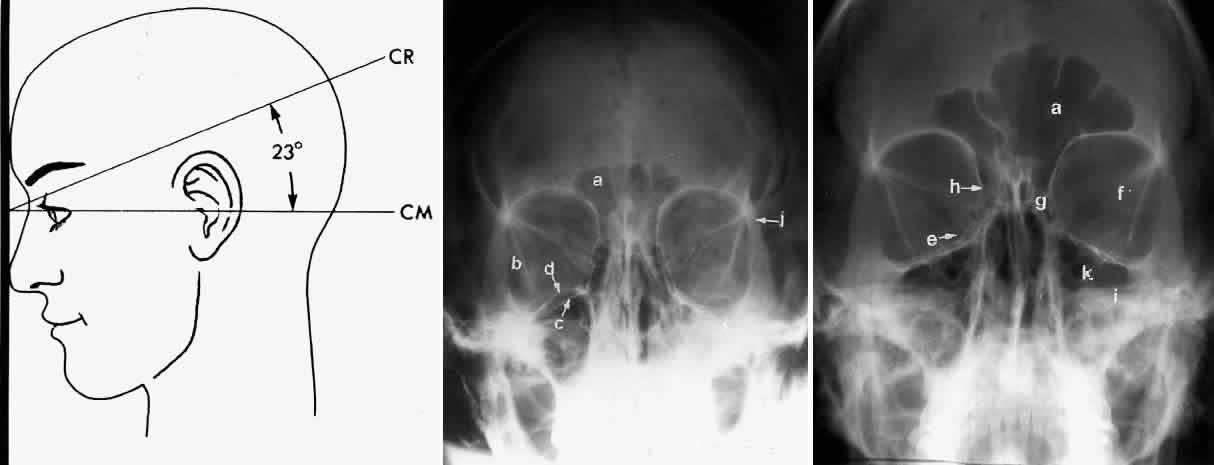

In an attempt to improve the visualization of the maxillary and ethmoid sinuses, in 1915 Waters and Waldron7 described a radiographic projection (Fig. 2) that eliminated the overlapping shadows of the dense petrous ridge of the temporal bone. Waters projection is created by placing the chin of the patient on the x-ray cassette with the canthomeatal line (the line that connects the lateral canthus and the external auditory meatus) at 37 degrees to 45 degrees.5,6 This orientation is accomplished if the nose of the patient is approximately 0.5 to 1.5 cm above the x-ray plate.7,8 A mnemonic is—the patient raises the chin up to sip water.

Fig. 2. A. Schematic showing positioning for a Waters projection. (CM, canthomeatal line; CR, central ray) B. Radiograph of a Waters projection. The petrous ridge lies below the maxillary sinus. (a, frontal sinus; b, medial orbital wall; c, innominate line; d, inferior orbital rim; e, orbital floor; f, maxillary antrum; g, superior orbital fissure; h, zygomatic-frontal suture; i, zygomatic arch) (A; Rao VM, Gonzalez CF: Plain film radiography and polytomography of the orbit. In Gonzalez CF, Becker MH, Flanagan JC [eds]: Diagnostic Imaging in Ophthalmology, pp 1–7. New York, Springer Verlag, 1986)

Waters view provides the best image of the maxillary antrum and good images of the orbital rim, orbital floor, zygomatic bones and arches, lesser wing of the sphenoid, and infraorbital foramen. This view is useful to the clinician in orbital floor fracture assessment because of the clear image of the orbital floor and the underlying maxillary sinus. The floor of the orbit should form a continuous radiographic line with the lateral wall of the orbit. Confusion can occur regarding the location of the orbital floor and its relationship to the orbital rim. The orbital floor is located inferior to the orbital rim not in the same plane, because of the orientation of the patient's head in Waters projection. A soft tissue density in the roof of the maxillary sinus or opacification of the floor of the sinus suggests an orbital floor disruption.